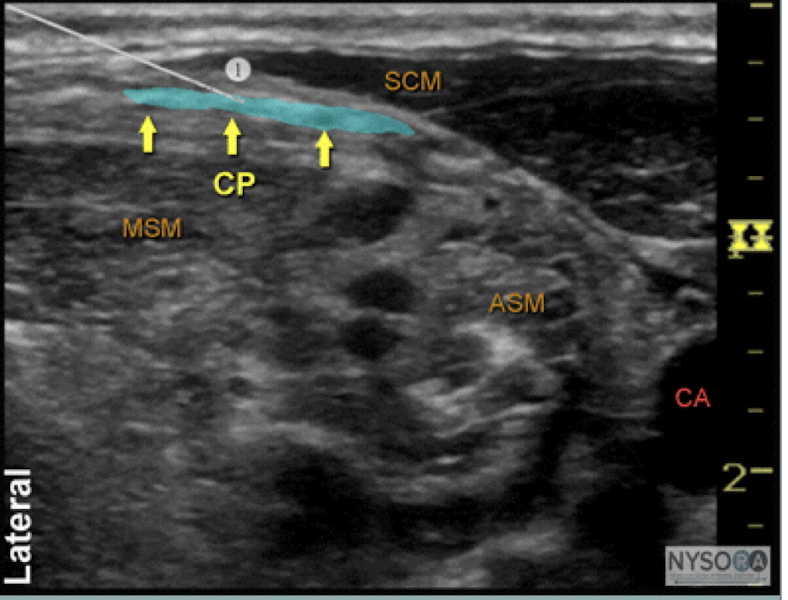

19

Q

What block and what structures?

A

superficial cervical plexus block

SCM

middle scalene muscle

cervical plexus

ant scalene

carotid artery

How well did you know this?